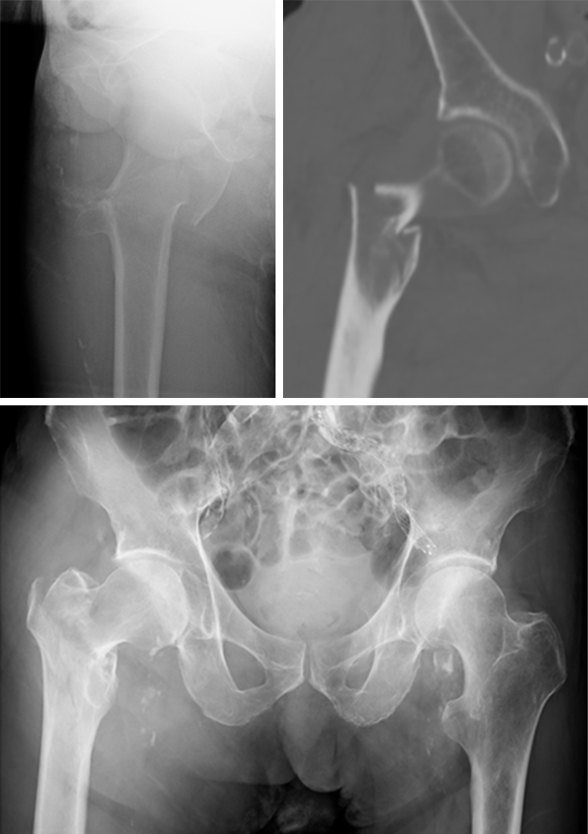

A 98-year-old female patient sustained a pertrochanteric fracture of the left proximal femur due to fall in her nursing home (Fig 1). There was significant pain and coxarthritis in the right hip, and hypertension. Surgery was performed within 24 hours. There was an indication for augmentation due to the instability of the fracture. The patient additionally suffered from osteoporosis and dementia.

Case provided by Hiroaki Minehara, Sagamihara, Japan